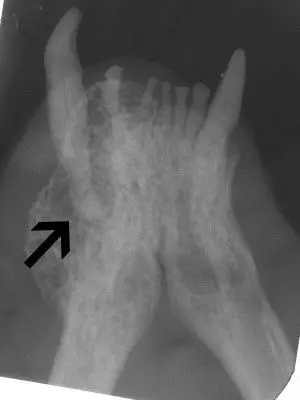

Type I resorption is seen in the root of 404 (arrow). This root requires complete removal. Type II resorption is seen in 304 and may be treated with crown amputation and intentional root resorption.

These roots show type I resorption and were inappropriately treated with intentional crown amputation. Note how distinct the roots are from the bone. The periodontal ligament can not be seen on some of these roots, but this alone is not reason enough to utilize the crown amputation technique.